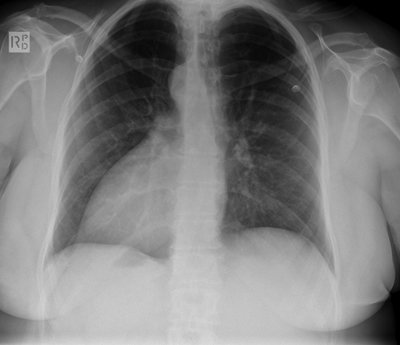

Il me semble que c'était la radio du situs inversus uniquement qui n'était pas disponible car l'ingé avait remonté le rideau trop tôt :p Les photos avaient été toutes montrées.

Du coup pour la radio, elle n'avait rien du tout de différent de celles trouvées sur google, c'était plus pour vous faire un petit "trouvez ce qu'à le patient", pas grand intérêt !

Voic quand même :)

cxrsitus.jpg